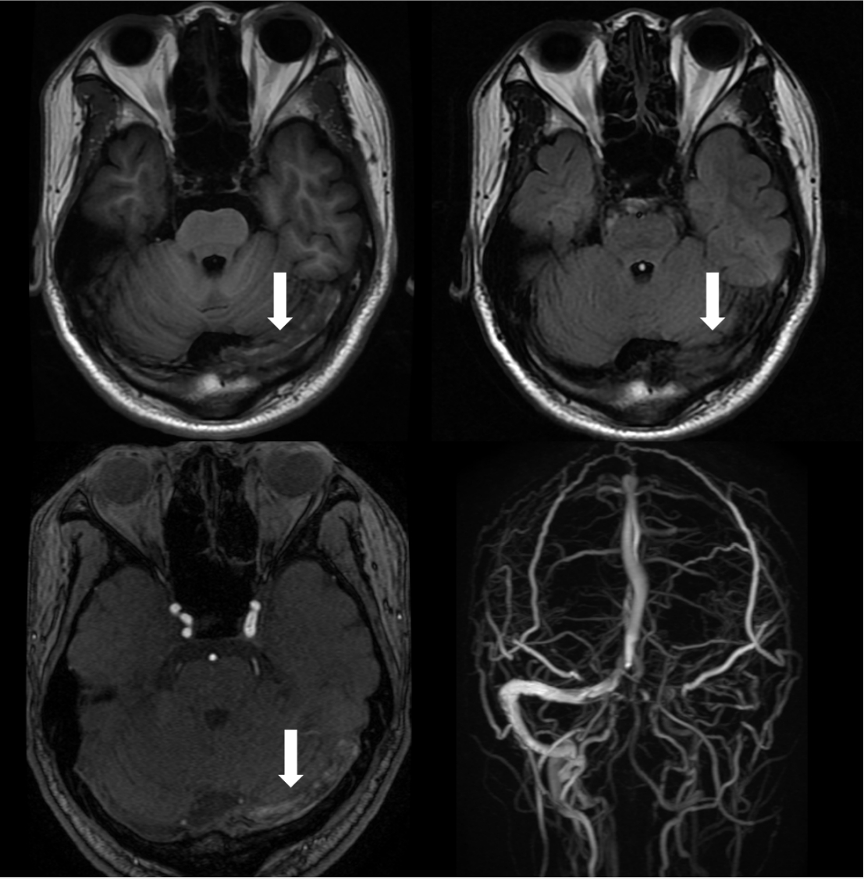

头MRI+MRV:左侧橫窦、乙状窦走形区异常信号,考虑为血栓。

复查静脉窦高分辨率MRI提示:左侧横窦、上矢状窦内血栓,左侧横窦内血栓量较前增加增加,复查腰穿压力290mmH2O,后转我科治疗。